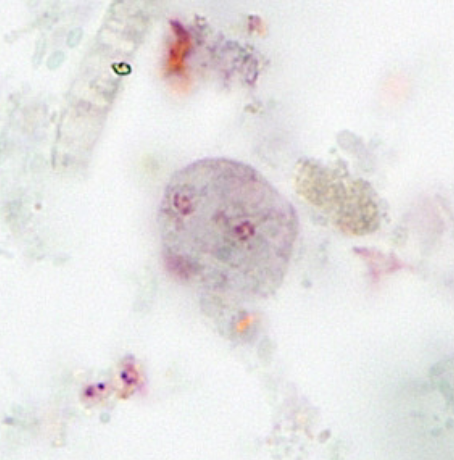

Entamoeba histolytica (cyst) >10

Entamoeba histolytica (cyst)

Entamoeba histolytica (cyst)

Entamoeba histolytica (troph)

Entamoeba histolytica (troph)